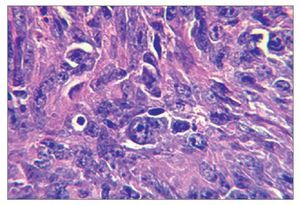

El examen histológico mostró un fuerte infiltrado difuso constituido por células blásticas linfoides grandes que presentaban núcleos ovoides y nucleolos prominentes, con presencia de numerosas mitosis atípicas (figs. 2a y 2b). La inmunohistoquímica mostró células pleomórficas positivas para CD20 y negativas para CD30, CD3, y anticuerpos Alk, confirmando el diagnóstico de LNH difuso de células B grandes (figs. 2c a 2f). Una vez completado el estudio se descartó linfoma sistémico.

Figura 2a. Infiltrado difuso de células blásticas con núcleos ovoides y nucleolos prominentes (hematoxilina-eosina; 40 aumentos originales).

Figura 2b. Campo que muestra mitosis atípicas (hematoxilina-eosina; 40 aumentos originales).